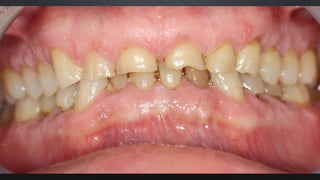

• OCLUSÃO HABITUAL, DETERMINADA PELOS DENTES

RELAÇÃO ENTRE ARCOS

MÁXIMA INTERCUSPIDAÇÃO HABITUAL (MIH)

• OCLUSÃO ONDE SE OBTÉM O MAIOR NÚMERO DE CONTATOS DENTAIS

POSSÍVEIS

• POSIÇÃO DE REABILITAÇÃO EM PACIENTES DENTADOS COM OCLUSÃO

ESTÁVEL